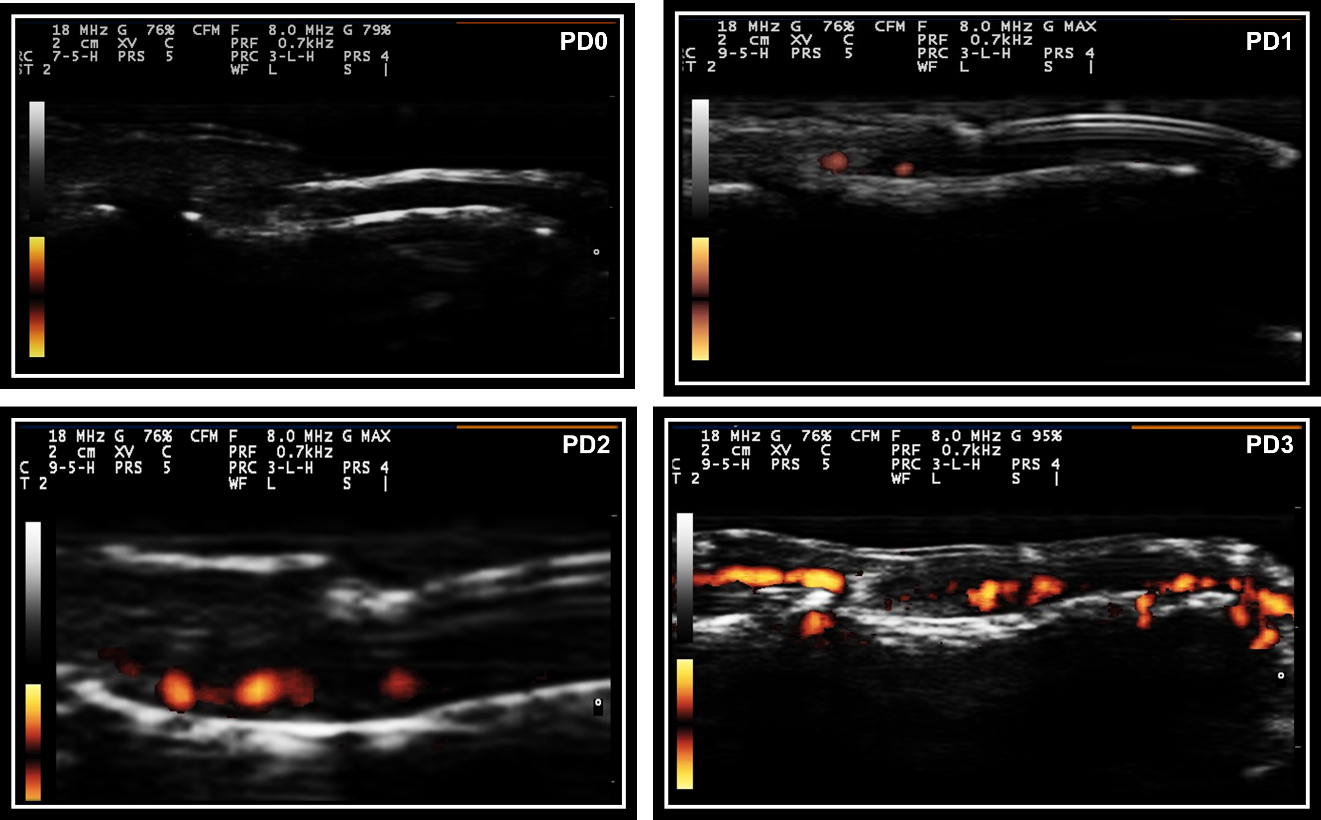

Nail abnormalities detected by US were graded with both GS and PD techniques. Nail abnormalities observed in the GS were semi-quantitatively graded from 0 to 3, as follows: GS0-preserved three-layered nail pattern; GS1-mild abnormality in the three-layered nail pattern or one sinuosity or nail loss; GS2-intense abnormality in the three-layered nail pattern, still preserving some segments of the nail, more than one sinuosity or nail loss; and GS3- total loss of the three-layered nail pattern, thickening of all the nail bed with loss of the eco texture or the nail insertion point (≥2.5 mm) (Figure 1). The nail bed (distance between the ventral plate and the bone margin of the distal phalanx) was measured in both the longitudinal plane (longitudinal mNGS, mm) and the transversal plane (transversal mNGS, mm). Nail PD abnormalities (PD0-3) were graded to measure the presence and intensity of nail enthesitis as follows: PD0: there is no in the nail bed flow; PD1: presence of 1 point or 25% of the PD signal especially at the insertion point of the nail; PD2: presence of <50% of the PD signal especially at the insertion point of the nail; PD3: presence of >50% of PD signal especially at the insertion point of the nail (Figure 2). sD was used to measure RI in the nail bed in both the longitudinal plane and the transversal plane (Figure 3).

Figure 2 Semiquantitative PD score for nail abnormalities.

Legend- PD0, Signal power Doppler grade 0; PD1, Signal power Doppler grade 1; PD2, Signal power Doppler grade 2; PD3, Signal power Doppler grade 3.